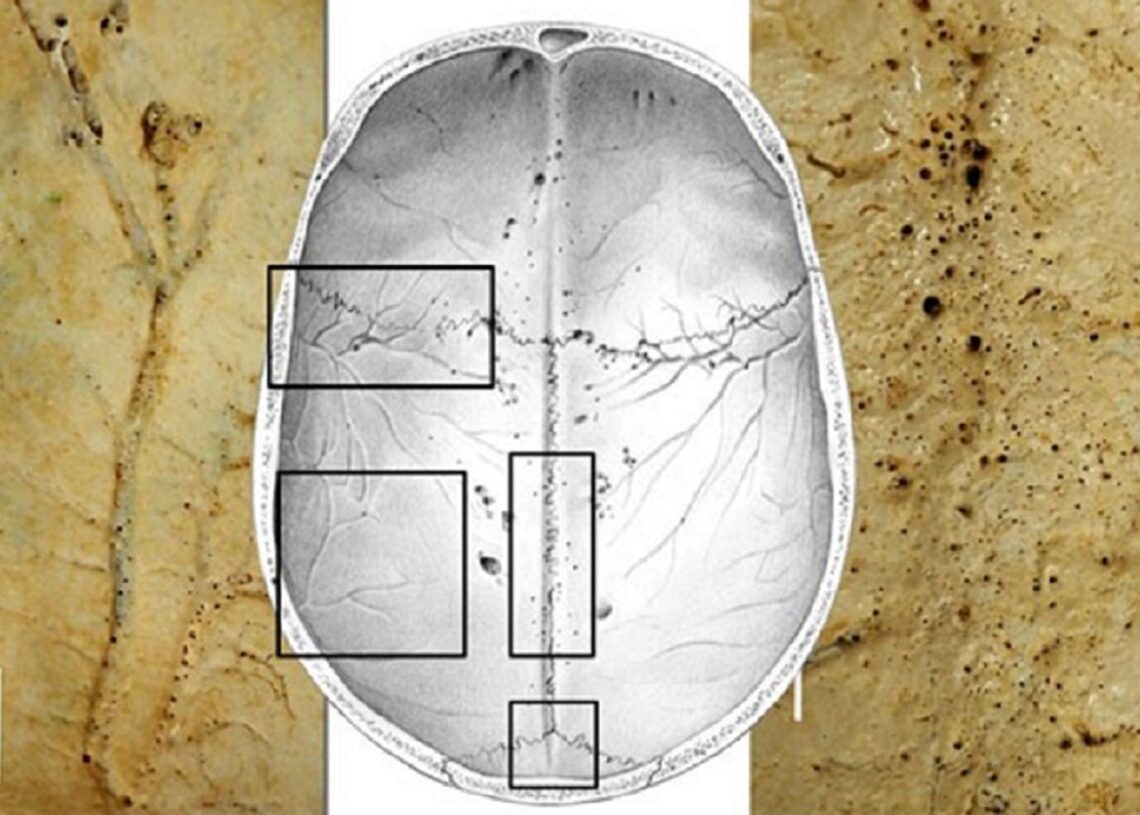

Los microforámenes son conductos vasculares diminutos, de entre 0,03 y 2 milímetros, que atraviesan los huesos craneales desde su capa interna hasta la superficie en contacto con las meninges. «La presencia de estos canales se mencionó en la literatura científica en los años 90, y hace tres años se reveló que estaban implicados en la respuesta inmunitaria e inflamatoria del cerebro, pero hasta hoy no teníamos una descripción formal de su apariencia, tamaño y distribución en el cráneo humano», explica Emiliano Bruner.

Bruner observó que la distribución de estos microcanales varía significativamente entre individuos, donde algunos cráneos mostraban solo unos pocos, mientras que otros tenían cientos. Además, «las variaciones individuales son notables, y cada sujeto tiene un patrón único en términos de tamaño y distribución de los microcanales», señala el investigador.

Las áreas con mayor densidad de estas estructuras se encuentran en la parte posterior de los huesos parietales y a lo largo de la sutura sagital. También se observaron numerosos microconductos en las áreas por donde pasan las arterias meníngeas medias.